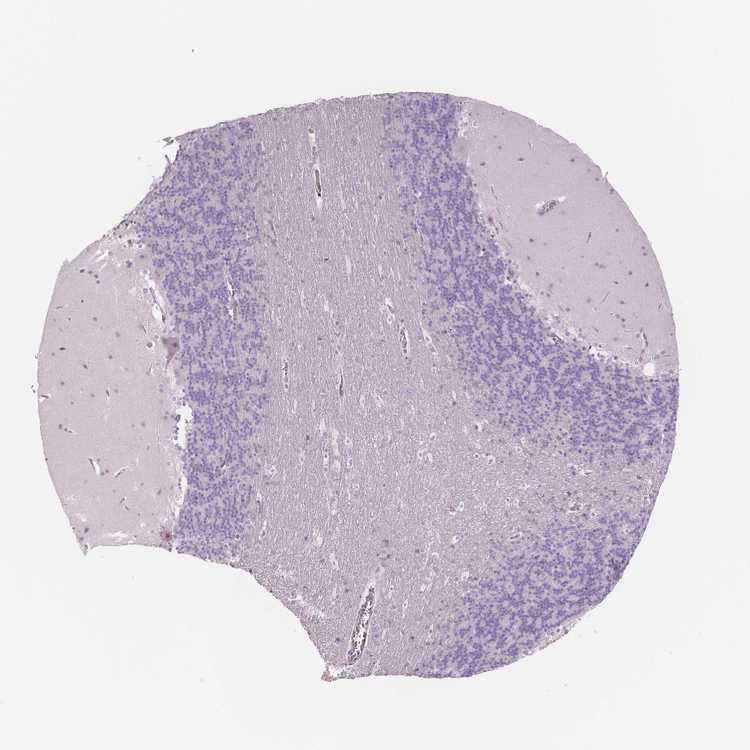

CEREBELLUM - Antibody stainingi

Antibody staining in the annotated cell types in the current human tissue is reported as not detected, low, medium, or high, based on conventional immunohistochemistry profiling in selected tissues. This score is based on the combination of the staining intensity and fraction of stained cells.

Each image is clickable and will lead to virtual microscopy that enables deeper exploration of all samples and also displays staining intensity scores, fraction scores and subcellular localization as well as patient and tissue information for each sample.

Antibody HPA001352Antibody HPA002549Antibody CAB068250Antibody CAB068251Antibody CAB068252

Purkinje cells Not detectedNot detectedNot detectedNot detectedNot detected

Cells in granular layer Not detectedNot detectedNot detectedNot detectedNot detected

Cells in molecular layer Not detectedNot detectedNot detectedNot detectedNot detected